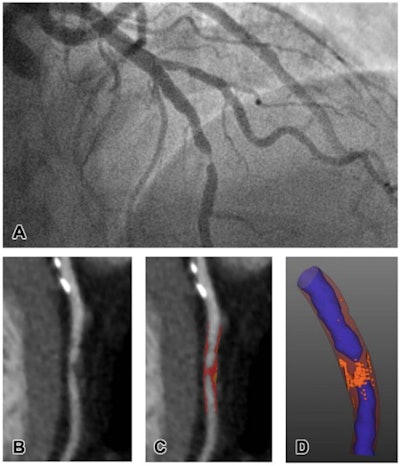

"CT-defined high-risk low-attenuation plaque can be used to risk stratify patients with coronary artery disease and is one of the strongest predictors of future myocardial infarction," they explained.

Meah and colleagues sought to confirm whether particular kinds of heart plaque characterized on CTCA could help clinicians determine the type of heart attack a patient was suffering via a study that included 327 patients. Of the total cohort, 155 had type 1 infarction, 36 had type 2, and 136 had chest pain but no heart attack.

CTCA results showed that patients with type 1 heart attack had greater total, noncalcified, and low-attenuation plaque burdens compared with those patients with type 2. The presence of low-attenuation plaque was confirmed to be an independent predictor of type 1 attack, with an odds ratio of 3.44 (1 is reference standard).

CTCA findings regarding plaque burden that distinguishes types of heart attack | ||

Type of plaque burden | Type 1 heart attack | Type 2 heart attack |

Total | 44% | 35% |

Noncalcified | 39% | 34% |

Low-attenuation | 4.1% | 1.6% |